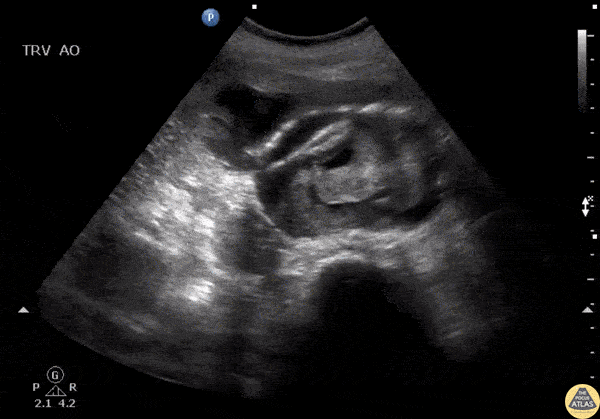

Aorta - Ruptured AAA

An elderly patient presented to the ED with hypotension and back pain and free intra-abdominal fluid seen on FAST exam. Ultrasound of the aorta revealed a rupture of an abdominal aortic aneurysm. Image courtesy of Robert Jones DO, FACEP @RJonesSonoEM Director, Emergency Ultrasound; MetroHealth Medical Center; Professor, Case Western Reserve Medical School, Cleveland, OH View his original post here